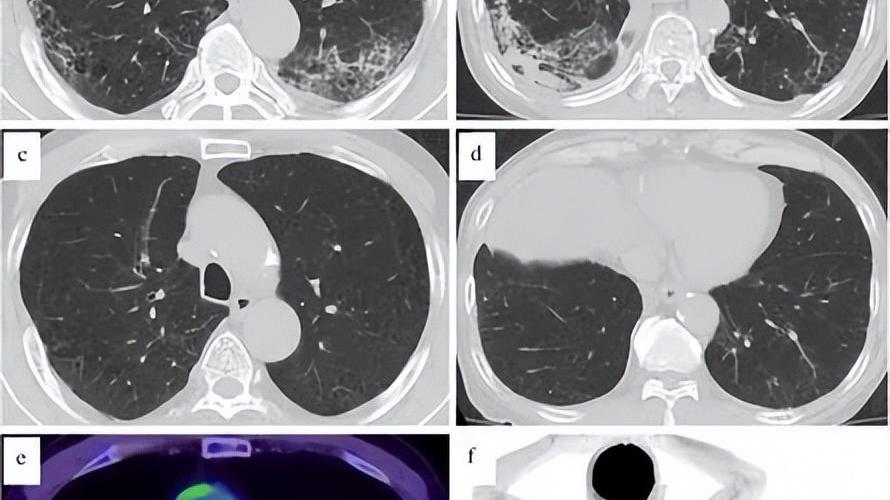

文章图片